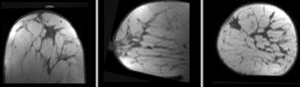

unregistered unregistered

affine registered affine

Bspline registered BSpline 9x9x4 max 15mm

Bspline registered Deformation field for BSpline 9x9x4 max 10mm

Bspline registered BSpline 7x7x5 max 10mm